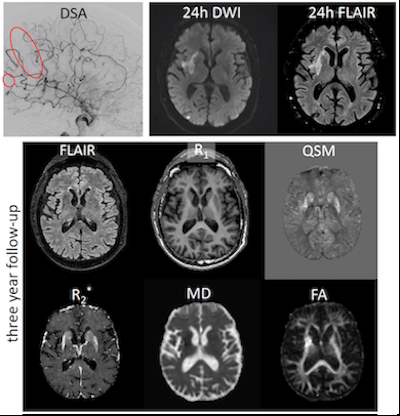

Three-year Follow-up Quantitative MRI And Recovery Assessment After Endovascular Treatment In Acute Ischemic Stroke

Abstract Body: Introduction: Long term (>36 months) recovery after endovascular treatment (EVT) remains largely understudied in acute ischemic stroke (AIS) patients. Previously, we have shown that long-term white matter microstructure damage, iron deposition and atrophy within/remote to the 24-hour stroke lesion could influence long term quality of life. However, the role of baseline and 24-hour lesion characteristics on long term lesion characteristics and the influence of lesion status on recovery to perform daily activities is unknown.

Methods: We executed a quantitative 3T MRI protocol (FLAIR, diffusion MRI, R1, R2*, Quantitative Susceptibility Mapping, Arterial Spin Labeling) after 37 (IQR: 28-38) months in patients from the MR CLEAN No-IV trial who received a 24-hour post-EVT MRI (DWI, FLAIR, SWI). Lateral ventricular volume difference was computed at both time-points to quantify atrophy. Long term MRI was also used to quantify iron deposition (R2*) and volume difference in subcortical nuclei relative to the contralateral nuclei. Long term recovery was defined using daily activity scores from EQ5D5 questionnaire. A Bayesian paired T-test of ventricular lateral atrophy between 24-hour and long term MRI was performed, and a Bayesian correlation of baseline clinical and 24-hour lesion characteristics with long term MRI outcomes (Bayes Factor (BF)<3: no/weak; BF>3: moderate; BF>20: strong evidence).

Results: We included 24 patients with a 24-hour and long-term MRI protocol. Median age was 64 (51-75) years, 11 (46%) patients were randomized to receive intravenous thrombolysis (IVT) prior to EVT, and 19 (79%) patients had an MCA occlusion. Functional independence (mRS 0-2) at 90 days (21 (88%) patients) and long term (20 (83%) patients) was comparable. Ventricular lateral atrophy was observed (BF=4.105), and higher baseline blood pressure and poorer collaterals were associated with larger long term lateral ventricular atrophy (BF: 11, 11, 4.3 respectively). Lower ASPECTS and poorer collaterals were associated with higher thalamic volume difference (BF=111, 11 respectively). Lastly, lower hippocampal volume and iron deposition were associated with reduced long term daily activity (BF=26, BF=4).

Conclusion: While functional independence in our cohort remains comparable over time, baseline, clinical, and treatment characteristics point to long-term brain degradation, which in turn impacts the ability of patients to perform daily activities.